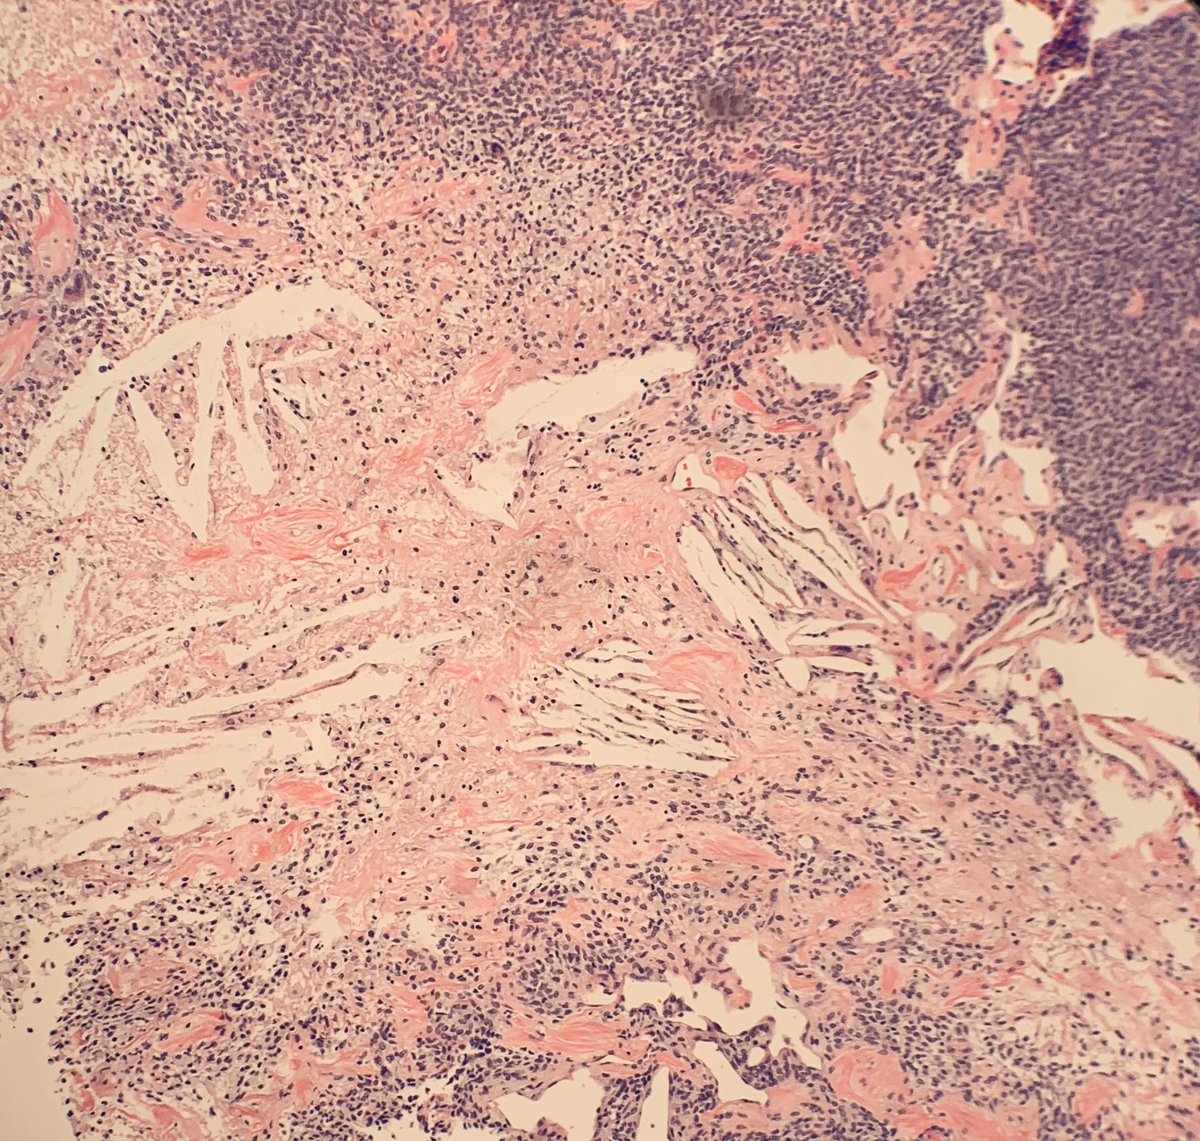

56 year old female with a right frontal mass. Immunos to come tomorrow. Differentials? Might have given it away with one specific image

#pathology#neuropath#neurosurgery#surgery#brain#CNSpic.twitter.com/RKdoqs1ZoH

Also cholesterol clefts are seen in areas that appear necrotic.... not sure what to make of that

any thoughts? #brain#neuropath#pathologypic.twitter.com/STt56WdINC

@goziemnweke posted the immunos. This is a grade 3 tumor with the hypercellularity, necrosis and >5 mitosis / 10 HPF.Prikaži ovu nitHvala. Twitter će to iskoristiti za poboljšanje vaše vremenske crte. PoništiPoništi -